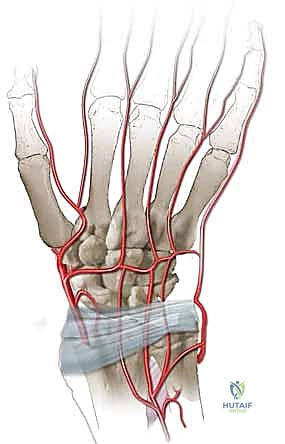

التروية الدموية: نقطة الضعف القاتلة

السبب الجذري لمرض كينبوك يكمن في التروية الدموية الفريدة (والهشة أحياناً) للعظم الهلالي. تتلقى معظم العظام الدم من عدة أوعية دموية تدخل من اتجاهات مختلفة. ومع ذلك، في حوالي 20% إلى 30% من البشر، يتلقى العظم الهلالي إمداده الدموي من وعاء دموي واحد فقط (Single Volar or Dorsal Artery). إذا تعرض هذا الوعاء الدموي الوحيد للانسداد، أو التمزق بسبب صدمة، أو الضغط المستمر، فإن العظم يُحرم من الأكسجين والمواد المغذية، مما يؤدي إلى بداية عملية النخر (موت الخلايا العظمية).

أولاً: جراحة زراعة الطعم العظمي الوعائي (Vascularized Bone Grafting)

الهدف من هذا الإجراء هو جلب دم جديد وصحي إلى العظم الهلالي الميت لإنقاذه من الانهيار والسماح له بإعادة بناء نفسه.

كيف تتم؟

إنها جراحة دقيقة (Microsurgery) تتطلب مهارة فائقة في التعامل مع الأنسجة الرقيقة والأوعية الدموية الدقيقة.

1. يقوم الدكتور هطيف بفتح شق جراحي دقيق في الرسغ (عادة من الناحية الظهرية أو البطنية حسب مصدر الطعم).

2. يتم تحديد قطعة صغيرة من العظم السليم من منطقة قريبة (غالباً من عظمة الكعبرة السفلية - Distal Radius).

3. الجزء الحاسم: لا يتم أخذ العظم فحسب، بل يتم استئصاله مع الشريان والوريد المتصلين به (Pedicled graft). هذا يعني أن قطعة العظم المنقولة لا تزال حية وتنبض بالدم.

4. يتم تنظيف العظم الهلالي الميت وتفريغه من الأنسجة الميتة (Core Decompression).

5. يُزرع الطعم العظمي الحي (الوعائي) داخل التجويف الذي تم إنشاؤه في العظم الهلالي.

6. تعمل الأوعية الدموية المنقولة كـ "شريان حياة" جديد، حيث تبدأ في تغذية العظم الهلالي، مما يحفز الخلايا العظمية (Osteoblasts) على بناء نسيج عظمي جديد وقوي.